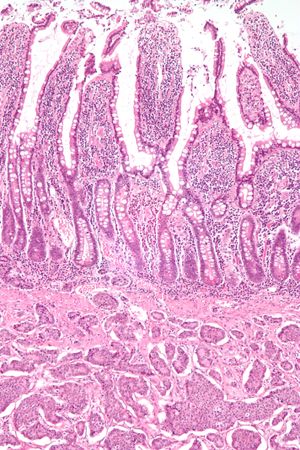

5. 3. 조직 병리학

신경내분비 병변은 세포의 모양보다는 세포가 얼마나 빨리 자라는지를 나타내는 표지에 따라 조직학적으로 등급이 매겨진다. 현재 세계 보건 기구(WHO)는 모든 위장관 및 췌장 신경내분비 종양에 대해 다음과 같은 등급 분류 체계를 권장한다.[36]

병리 진단 시에는 우선 현미경으로 세포 형태의 이상 유무를 관찰한다. 또한, 특정 단백질에 반응하는 항체를 이용하여 종양 세포를 식별하는 면역 염색(Immunostaining) 방법을 사용하기도 한다.[106] 면역 염색은 특정 단백질의 존재 유무를 색깔로 나타내어 현미경 관찰을 용이하게 한다.[107] 신경내분비 종양의 병리 진단에 사용될 수 있는 면역 염색 표지자의 예는 다음과 같다.